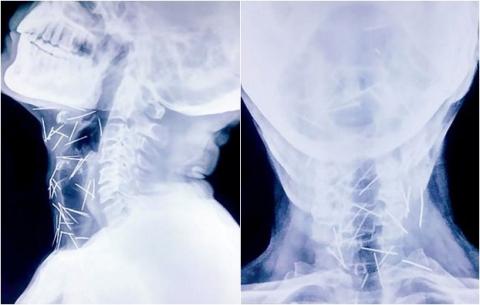

Kết quả chụp X-quang cho thấy có đến 75 cây kim trong cơ thể của

ông Badrilal Meena.

Kết quả chụp X-quang ghi nhận, bên trong bàn chân của ông Meena có nhiều cây kim sắc nhọn. Không những vậy, bác sĩ còn phát hiện ra rất nhiều kim ở cánh tay và cổ của bệnh nhân, tổng cộng có đến 75 cây.

Có 40 cây nằm trong cổ họng, 25 cây ở chân phải, số còn lại nằm ở hai

cánh tay.

Trong số 75 cây kim tìm thấy trong cơ thể ông Meena, có 40 cây nằm trong cổ họng, 25 cây ở chân phải, số còn lại nằm ở hai cánh tay.